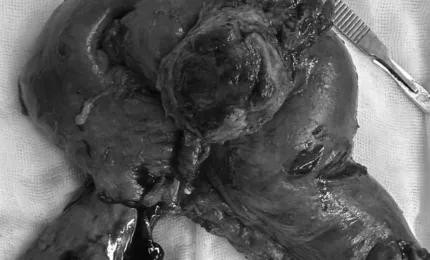

Nỗ lực giành sự sống của bệnh nhân ung thư gan giai đoạn cuối

Ung thư gan giai đoạn cuối kèm theo hàng loạt biến chứng như tắc mật, nhiễm trùng huyết, nhiễm nấm phổi, suy đa cơ qu